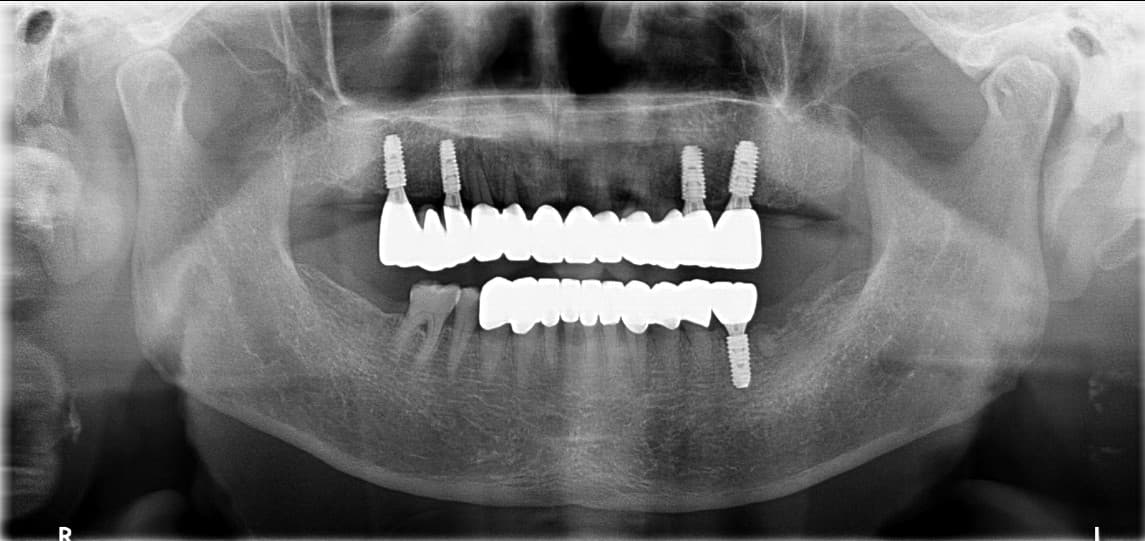

REAL PATIENT RESULTS

To'liq implant

oldin va keyin

Haqiqiy bemorlarimizning ajoyib o'zgarishlarini ko'ring

Kim●● · 60 yoshdan oshgan erkak

Yuqori jag to'liq implant

After ✨

Lee●● · 60 yoshdan oshgan ayol